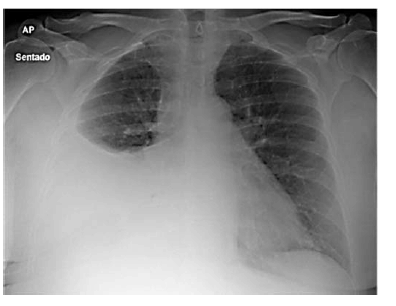

Paciente do sexo feminino, de 27 anos de idade, casada, técnica de enfermagem de uma unidade de pronto atendimento (UPA), comparece ao setor de emergência com queixa de dispneia havia 1 semana e indisposição, havia 1 mês. Era tabagista ativa e não fazia uso de medicações regularmente. Na história ginecológica da paciente, não havia particularidades, a anticoncepção era realizada com preservativo masculino. Ao exame físico, apresentou-se em bom estado geral, hidratada e com sinais vitais estáveis. ausculta pulmonar, o murmúrio estava abolido no terço inferior do hemitórax direito. Nos exames complementares, o hemograma estava normal, as sorologias negativas. A imagem a seguir mostra o Raio X de tórax da paciente.

Paciente do sexo feminino, de 27 anos de idade, casada, técnica de enfermagem de uma unidade de pronto atendimento (UPA), comparece ao setor de emergência com queixa de dispneia havia 1 semana e indisposição, havia 1 mês. Era tabagista ativa e não fazia uso de medicações regularmente. Na história ginecológica da paciente, não havia particularidades, a anticoncepção era realizada com preservativo masculino. Ao exame físico, apresentou-se em bom estado geral, hidratada e com sinais vitais estáveis. ausculta pulmonar, o murmúrio estava abolido no terço inferior do hemitórax direito. Nos exames complementares, o hemograma estava normal, as sorologias negativas. A imagem a seguir mostra o Raio X de tórax da paciente.

Paciente do sexo feminino, de 27 anos de idade, casada, técnica de enfermagem de uma unidade de pronto atendimento (UPA), comparece ao setor de emergência com queixa de dispneia havia 1 semana e indisposição, havia 1 mês. Era tabagista ativa e não fazia uso de medicações regularmente. Na história ginecológica da paciente, não havia particularidades, a anticoncepção era realizada com preservativo masculino. Ao exame físico, apresentou-se em bom estado geral, hidratada e com sinais vitais estáveis. ausculta pulmonar, o murmúrio estava abolido no terço inferior do hemitórax direito. Nos exames complementares, o hemograma estava normal, as sorologias negativas. A imagem a seguir mostra o Raio X de tórax da paciente.

Paciente do sexo feminino, de 27 anos de idade, casada, técnica de enfermagem de uma unidade de pronto atendimento (UPA), comparece ao setor de emergência com queixa de dispneia havia 1 semana e indisposição, havia 1 mês. Era tabagista ativa e não fazia uso de medicações regularmente. Na história ginecológica da paciente, não havia particularidades, a anticoncepção era realizada com preservativo masculino. Ao exame físico, apresentou-se em bom estado geral, hidratada e com sinais vitais estáveis. ausculta pulmonar, o murmúrio estava abolido no terço inferior do hemitórax direito. Nos exames complementares, o hemograma estava normal, as sorologias negativas. A imagem a seguir mostra o Raio X de tórax da paciente.

Paciente do sexo feminino, de 27 anos de idade, casada, técnica de enfermagem de uma unidade de pronto atendimento (UPA), comparece ao setor de emergência com queixa de dispneia havia 1 semana e indisposição, havia 1 mês. Era tabagista ativa e não fazia uso de medicações regularmente. Na história ginecológica da paciente, não havia particularidades, a anticoncepção era realizada com preservativo masculino. Ao exame físico, apresentou-se em bom estado geral, hidratada e com sinais vitais estáveis. ausculta pulmonar, o murmúrio estava abolido no terço inferior do hemitórax direito. Nos exames complementares, o hemograma estava normal, as sorologias negativas. A imagem a seguir mostra o Raio X de tórax da paciente.

Paciente do sexo feminino, de 27 anos de idade, casada, técnica de enfermagem de uma unidade de pronto atendimento (UPA), comparece ao setor de emergência com queixa de dispneia havia 1 semana e indisposição, havia 1 mês. Era tabagista ativa e não fazia uso de medicações regularmente. Na história ginecológica da paciente, não havia particularidades, a anticoncepção era realizada com preservativo masculino. Ao exame físico, apresentou-se em bom estado geral, hidratada e com sinais vitais estáveis. ausculta pulmonar, o murmúrio estava abolido no terço inferior do hemitórax direito. Nos exames complementares, o hemograma estava normal, as sorologias negativas. A imagem a seguir mostra o Raio X de tórax da paciente.